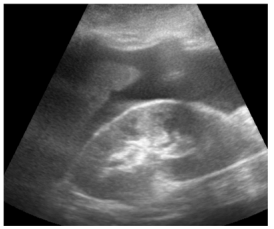

Insonação cardíaca Janela apical 5 câmaras com VTI de 9,08 cm

O nefrologista foi chamado a opinar na melhor conduta para o paciente. Para tanto, realizou uma ultrassonografia beira leito pulmonar e mensurou a velocidade integral tempo (VTI) do trato de saída do ventrículo esquerdo. Chegou, assim, à conclusão que poderia ser feita uma expansão no paciente. Com base nas imagens apresentadas, é correto afirmar que conduta recomendada pelo nefrologista está